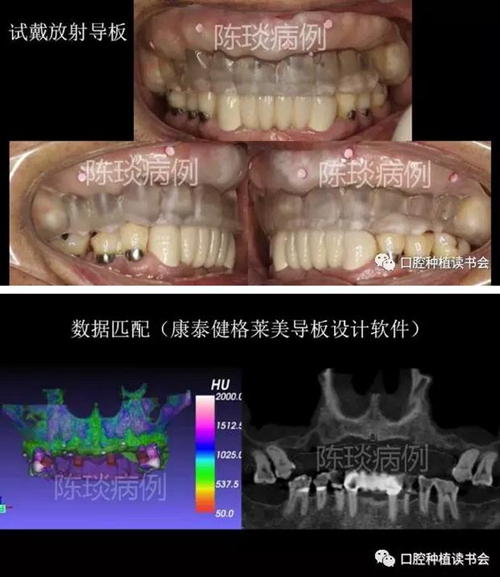

(1)制作臨時義齒以及放射導板,根據(jù)石膏模型設計放射導板,并確定顯影標記。

3.jpg

(2)佩戴放射導板拍CBCT后,設計數(shù)字種植導板。

4.jpg